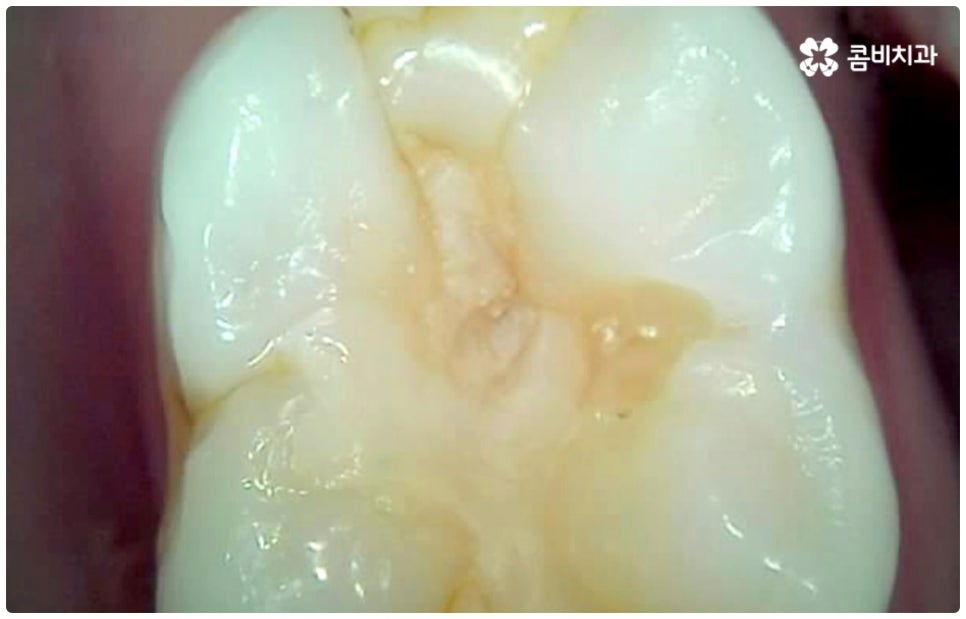

충치는 하루 아침에 생기는 것이 아니라 단계적으로 발전하는 구강 질환이며 시간이 지난다고해서 자연적으로 나아지지 않기 때문에 초기에 적절한 치료를 하지 않고 방치하게 되면 치아 손상이 점점 더 커지게 되고 결국 치아 상실까지 일으킬 수 있어 주의하실 필요가 있는데요. 충치를 초기에 발견하고 충치치료종류 중 레진으로 직접 때우는 치료를 하면 보다 빠르고 간편한데도 불구하고 대부분의 환자분들이 이 시기에 제대로 대처하지 못하는 이유는 충치가 처음 발병하는 치아의 가장 바깥쪽 겉면 (법랑질) 에는 신경이 없기 때문에 환자분들이 통증 등 이상 현상을 느끼지 못하는 경우가 많고 또한 겉으로 보기에도 초기에는 충치로 인한 치아의 색상이나 모양 변화가 뚜렷하지 않아 놓칠 가능성이 높기 때문일 거예요. 초기에는 흔히 알고 계시는 충치 증상처럼 치아 일부가 검게 벌레먹은 듯 보이거나 치아 형태가 조금씩 무너지면서 구멍이 뚫린 것처럼 되지 않고 작고 불투명한 흰 점 또는 옅은 갈색 줄이 생긴 것처럼 느껴지기 때문에 알아차리기 힘들며 그마저도 육안으로 확인하기 어려운 곳 (구강 안쪽이나 치아 사이, 보철물 안쪽) 이라면 발견조차 못할 수 있어요.

그렇기 때문에 많은 분들이 일반적으로 시린 통증을 느낄 때 치과를 방문하게 되는데, 이 때는 이미 충치균이 치아의 단단한 겉면인 법랑질을 뚫고 상아질까지 침투한 단계일 가능성이 높으니 더 늦기 전에 바로 필요한 처치를 해 주실 필요가 있습니다. 상황에 따라 다르지만 보통 이 단계에서는 레진으로 직접 때워주는 치료가 적합하지 않은 경우가 많기 때문에 그럴 때는 충치치료종류 중 인레이 온레이와 같은 보철물을 이용하여 도움을 받을 수 있는데요. 이러한 치료는 손상된 부위를 깔끔하게 삭제한 후에 그 범위와 정도에 따라 빈 공간에 맞춤 제작한 보철물을 채워넣는 것으로 (인레이는 상대적으로 깊고 좁은 부위에, 온레이는 교두를 포함한 좀 더 넓은 부위에 적용), 재질 역시 다양한 가운데 치아의 위치 및 역할, 그리고 환자분들의 경제적 상황 등 여러 가지를 고려하여 가장 잘 맞는 것으로 선택하면 되니 꼼꼼한 검진 후 담당의 선생님과 각 재질의 장단점에 대해 사전 상담을 충분하게 해 보시고 신중한 결정을 내리시길 권유드리고 있어요.